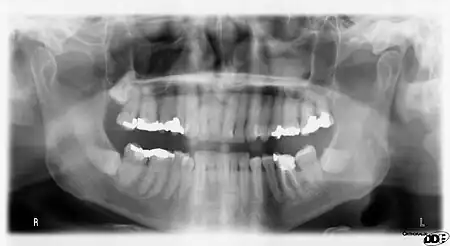

|  A dental panoramic radiograph, showing the maxilla and mandible, all the teeth including the "wisdom teeth," the frontal and maxillary sinuses, the nasal cavity and the temporomandibular joint and other near by head and neck anatomy. | |

A panoramic radiograph is a panoramic scanning dental X-ray of the upper and lower jaw. It shows a two-dimensional view of a half-circle from ear to ear. Panoramic radiography is a form of focal plane tomography; thus, images of multiple planes are taken to make up the composite panoramic image, where the maxilla and mandible are in the focal trough and the structures that are superficial and deep to the trough are blurred.